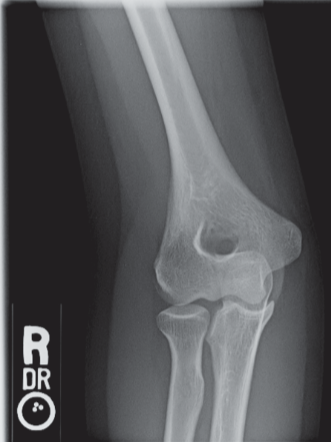

In which of the following projections was the image in Figure 6-1 made?

C) Lateral/external oblique

Feedback:

Figure 6-1 illustrates an oblique view of the proximal radius and ulna and distal humerus with epicondyles 45° to the IR—the external oblique (lateral rotation) projection is shown demonstrating the radial head free of superimposition as well as the radial neck, tuberosity, and the humeral capitulum.

The medial oblique (internal rotation) projection of the elbow is particularly useful to demonstrate the coronoid process in profile, the trochlea, and the medial epicondyle.

The acute flexion projection (Jones method) of the elbow is a two-projection method demonstrating the elbow anatomy when the part cannot be extended for an AP projection.